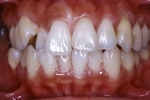

治療前後の比較